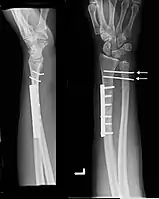

Images

Galeazzi fracture after surgical fixation